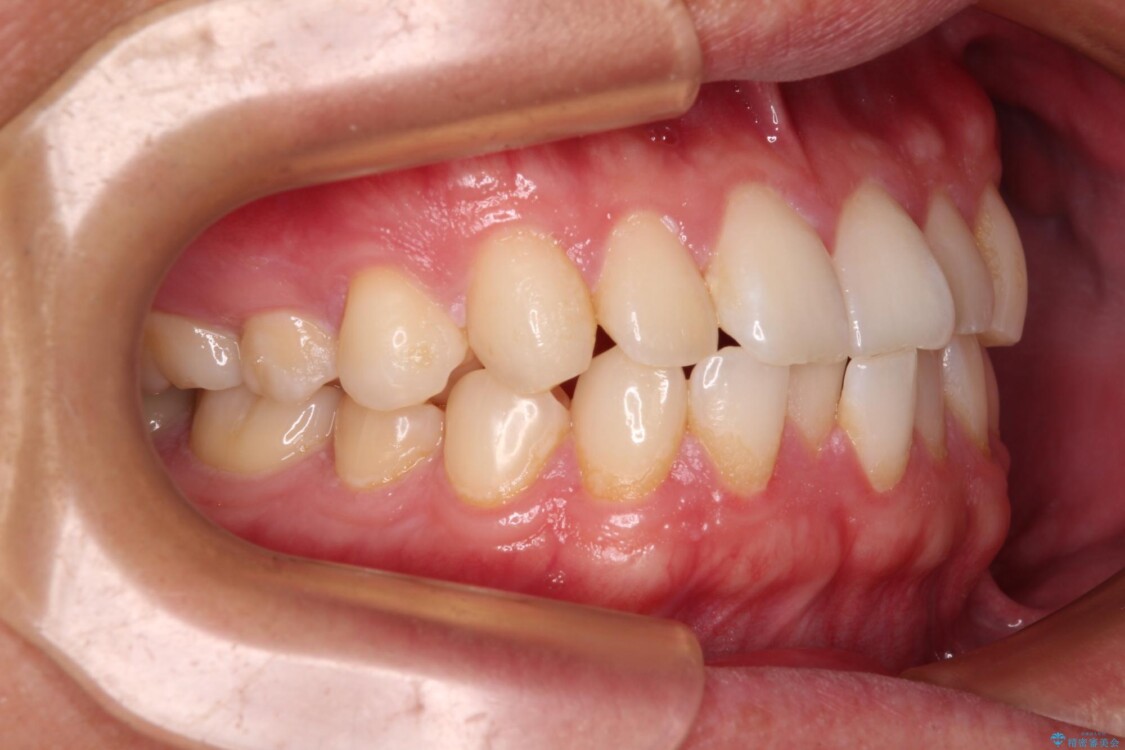

**前歯のデコボコ(叢生)**が整い、歯列全体が美しく改善

シザーズバイトの奥歯も正常なかみ合わせに改善

捻転歯も回転が修正され、全体的に清掃性・咀嚼効率が向上

治療後

• 前歯のガタガタ・奥歯のかみ合わせ(シザーズバイト)を改善|1年半で完了したメタルブラケット矯正 治療後画像